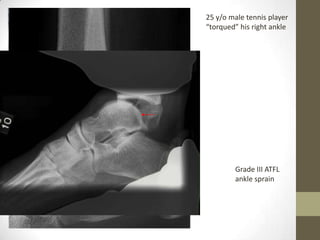

25 y/o male tennis player

“torqued” his right ankle

Grade III ATFL

ankle sprain